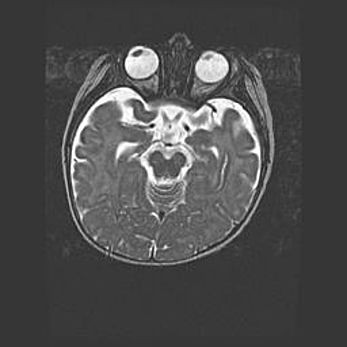

Лейкомаляция с кистозно-глиозной дегенерацией головного мозга.

Возраст: 2 месяца 25 дней

Вес: 6400 г

Окружность головы: 40 см

Срок гестации: 41 неделя

Лейкомаляцию относят к ишемически-гипоксическим повреждениям головного мозга, диагностируемым у новорожденных. При лейкомаляции в головном мозге обнаруживают очаги некроза, возникшие после тяжелой гипоксии и нарушения кровотока. В процессе морфогенеза очаги проходят три стадии: 1) развития некроза, 2) резорбции и 3) формирования глиозного рубца или кисты. Перивентрикулярная лейкомаляция (ПЛ) встречается примерно в 12% случаев среди новорожденных, обычно – у недоношенных детей, причем, частота ее зависит от массы, с которой младенец появился на свет. Наибольшее число малышей страдает лейкомаляцией, если масса при рождении 1500-2500 г.